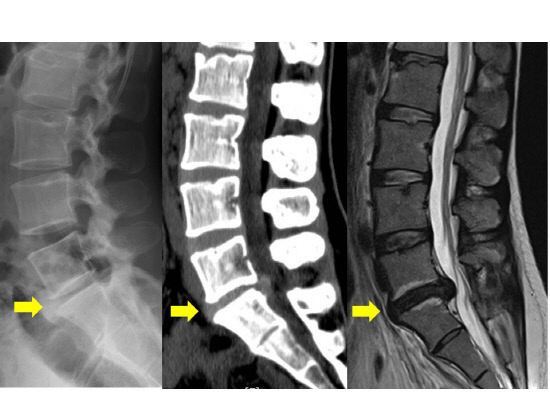

허리디스크는 현대인에게 매우 흔한 문제이며, 이를 통해 다양한 증상이 나타날 수 있습니다. 허리디스크, 즉 추간판 탈출증은 척추 디스크가 돌출되거나 파열되어 신경을 압박하게 되는 상황을 말합니다. 이로 인해 통증과 불편함이 발생하며, 일상생활에 큰 지장을 줄 수 있습니다.

두 번째 증상으로는 다리로 방사되는 통증, 즉 방사통이 있습니다.

허리에서 시작된 통증이 엉덩이와 다리로 퍼지는 경우가 많으며, 이는 디스크가 신경을 압박하기 때문입니다.